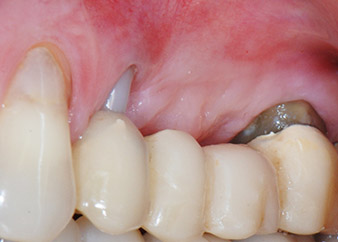

Infine, dopo incisione periostale, il sito è stato chiuso con suturazione passiva con un lembo avanzato a livello coronale, utilizzando materiale assorbile 5-0 da sutura (Fig. 15). La radiografia postoperatoria mostrava entrambi gli impianti nella loro posizione verticale corretta (Fig. 16).

Sito chirurgico dopo sutura tension free

Fig. 15: Sito chirurgico dopo sutura tension free con materiale assorbibile. Dopo sei mesi gli impianti sono stati esposti per un controllo.

Risultati intermedi dopo due mesi

Le figure 17 e 18 mostrano il risultato clinico due mesi dopo l'intervento chirurgico. Il dente 24 mostra mobilità ridotta di classe 1 secondo Miller e i tessuti molli sono privi di infiammazione. A questo punto l'utilizzo della sonda è stato evitato per impedire una nuova infezione e per non disturbare l'attacco epiteliale. Era stata programmata una visita di controllo al rientro e il posizionamento dei perni di guarigione sei mesi dopo l'inserimento degli impianti.

Due mesi dopo l'intervento chirurgico il paziente non lamentava dolore.

Fig. 17: Due mesi dopo l'intervento chirurgico, il paziente non lamentava dolore e l'area non presentava infiammazione.

dopo l'intervento chirurgico

Fig. 18: Il dente 24 ora mostrava minore mobilità.